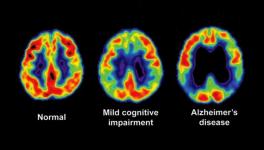

In a new study published in the journal Neuron, scientists have used brain maps to see the connections in it in order to predict how brain atrophy would spread in individual patients suffering from FTD. The study’s findings suggest that dementia spreads through the synaptic connections between established brain networks. The findings add to the growing evidence that dementia spreads through brain connections.

The corresponding author of the study, Willliam Seeley, a professor of neurology and pathology at the Memory and Ageing Centre and Weill Institute, has shown in his previous researches that brain atrophy in many forms of dementia is closely related to well-known brain networks. That is, group of functionally related brain regions that work cooperatively through their synaptic connections, sometimes even over long distances. In other words, these researches propose that instead of spreading evenly through the brain like that of a tumour, the neurodegenerative diseases jump from one part of the brain to another along the circuits that wire theses network together. The new study supports this idea.

They used the results from this step to predict in which direction the atrophy spreads and matched their predictions with the brain scans from the FTD affected people taken a year back. They found good matches in their predictions that were based on their hypothesis. The brain atrophy spreads through the brain by synaptic connections between related brain areas. The progression starts from a vulnerable region and eventually affects other parts.